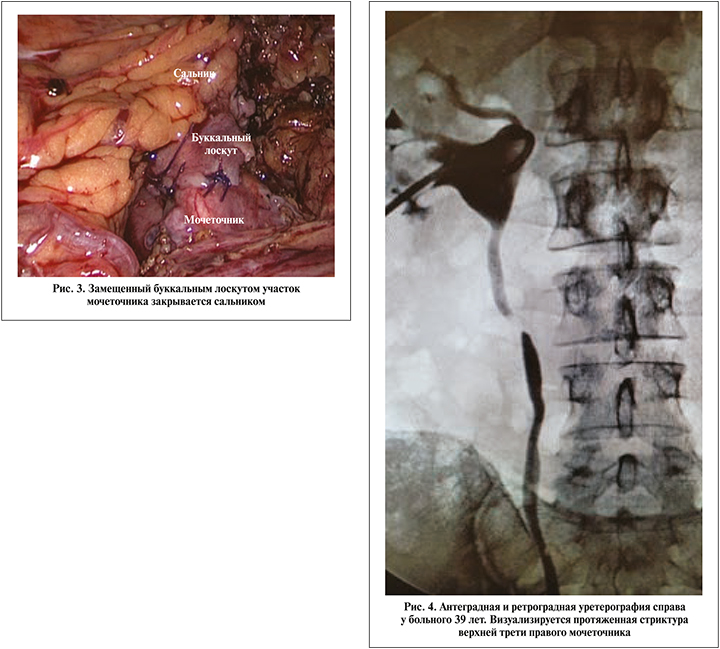

Приводим клиническое наблюдение успешной лапароскопической буккальной пластики верхней трети правого мочеточника.

Больной Б. 39 лет 09.07.2019 госпитализирован в клинику с диагнозом «стриктура верхней трети правого мочеточника, нефростома справа». Из анамнеза известно, что в декабре 2018 г. был в экстренном порядке госпитализирован с диагнозом «мочекаменная болезнь, камень средней трети правого мочеточника, почечная колика справа». При обследовании выявлен рентген-позитивный камень размером примерно 11 мм. Установлен стент, проведено два сеанса дистанционной литотрипсии без положительного эффекта. В январе 2019 г. в плановом порядке выполнена контактная лазерная уретеролитотрипсия справа, после которой часть камня мигрировала в чашечно-лоханочную систему. По этой причине вновь установлен стент и пациент выписан на амбулаторное лечение. В марте 2019 г. повторная госпитализация, в ходе которой выполнена лазерная контактная литотрипсия, конкремент полностью фрагментирован и удален. В апреле 2019 г. мочеточниковый стент извлечен. Однако через месяц вновь развился приступ почечной колики, при КТ брюшной полости с контрастированием данных за камень мочеточника не получено, выявлена стриктура верхней трети правого мочеточника. При диагностической уретероскопии на этом уровне выявлена облитерация. Выполнена перкутанная нефростомия справа. При антеградной пиелографии и ретроградной уретерографии визуализировалась протяженная стриктура проксимальной части правого мочеточника длиной около 3 см (рис. 4). 09.07.2019 в нашей клинике выполнена лапароскопическая буккальная пластика верхней трети правого мочеточника по вышеописанной методике (рис. 5). Длительность операции составила 180 мин, кровопотеря – 50 мл. Осложнений не было, дренаж удален на 3-е сутки и на 6-й день выписан на амбулаторное лечение. Стент извлечен через 6 нед. При антеградной пиелографии и по данным КТ проходимость правого мочеточника хорошая, нарушений уродинамики нет (рис. 6, 7). В течение периода наблюдения (8 мес.) состояние пациента стабильное, жалоб нет.